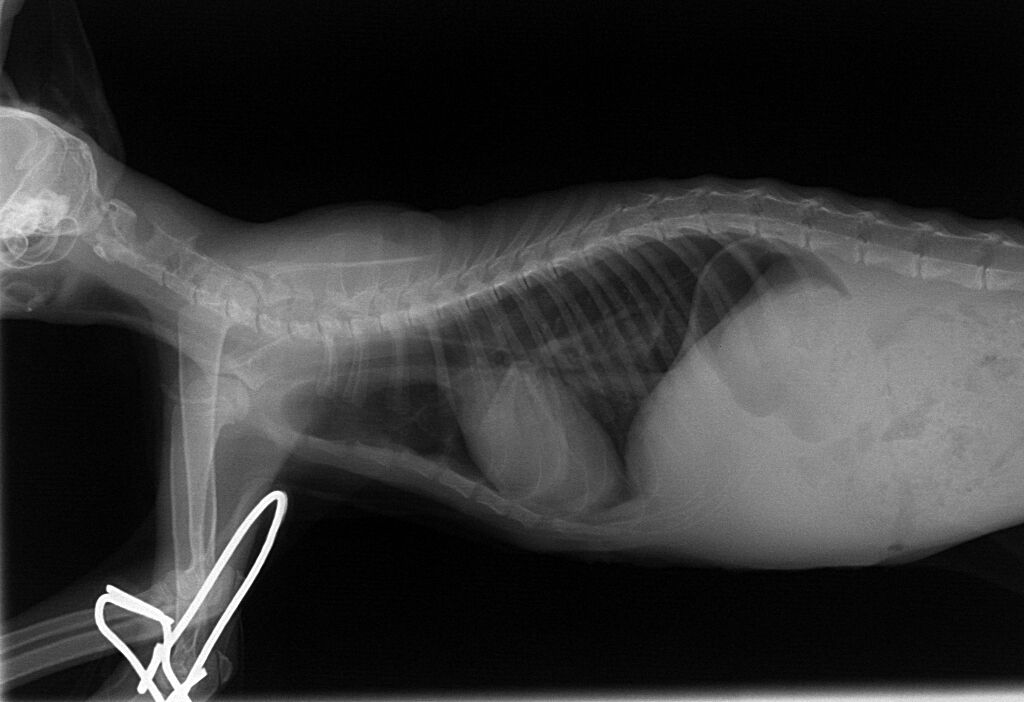

下の写真が術後のレントゲン写真です。左の肺は押しつぶされているのがわかります。術後の麻酔の醒めが極端に悪く、回復するか心配されました。翌日もよく寝ていましたが、徐々に回復の兆しは見えてきてました。

食欲はありませんでしたが、ICU内にて点滴と酸素供給を続け1日、2日と経つうちに徐々に起きている時間が長くなり、3日後には、ICUから出ても呼吸は安定し、食欲が出てきました。7日後にはほぼ正常になり、フードもよく食べて体重もどんどん増えてきました。そこで、レントゲンを撮り、その結果が下の写真です。

押しつぶされて小さくなっていた左の肺はきれいに全体に広がっているのがわかります。これでもう安心できる状態でした。その後、1週間くらい入院して、退院後、先住の他の猫ちゃんとも仲良く、家族のみなさんに大切に育てられています。